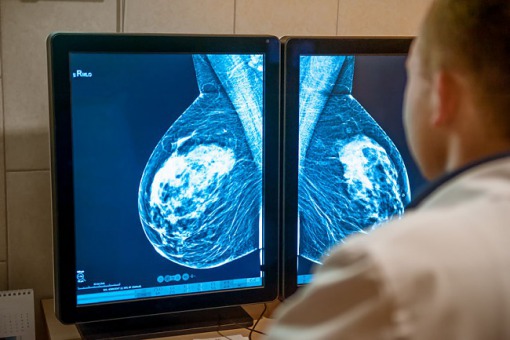

Według Światowej Organizacji Zdrowia (WHO) rak piersi stanowi prawie 12 proc. (w 2020 r. wykryto 2,3 mln przypadków) wszystkich nowotworów na świecie – wynika z najnowszych danych opublikowanych przez WHO z okazji przypadającego 4 lutego Światowego Dnia Raka.

– Rak piersi pod względem epidemiologii wyprzedził raka płuca, który przez ostatnie dwie dekady był najczęściej występującym i nadal pozostaje najbardziej śmiertelnym nowotworem. Na trzecim miejscu pod względem epidemiologii jest rak jelita grubego – powiedział Andre Ilbawi, ekspert WHO do spraw nowotworów .

Światowa Organizacja Zdrowia zwraca też uwagę, że pandemia COVID-19 w 2020 r. dodatkowo pogorszyła walkę z chorobami nowotworowymi. Spowodowane jest to zakłóceniami w terapii i w badaniach profilaktycznych, takich jak cytologia, mammografia i kolonoskopia.